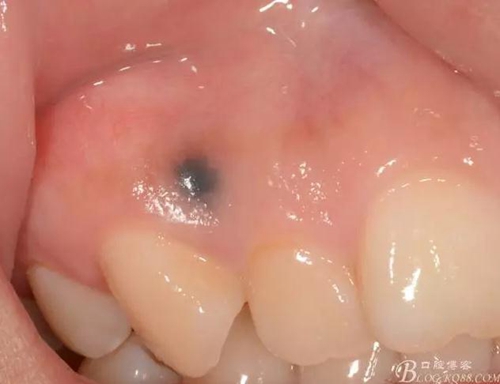

檢查:口腔衛(wèi)生尚佳,軟垢少量,牙石(+),色素沉著少量,全口牙齦色粉,質(zhì)地韌,BOP(+-),BI=0-1,全口PD=1-3mm左右,12,13唇側(cè)附著齦根尖方向處可見圓形色素沉著區(qū)(墨水沉積所致),其余黏膜以及唇紅未見異常,全口牙列未見明顯齲損。

術(shù)前